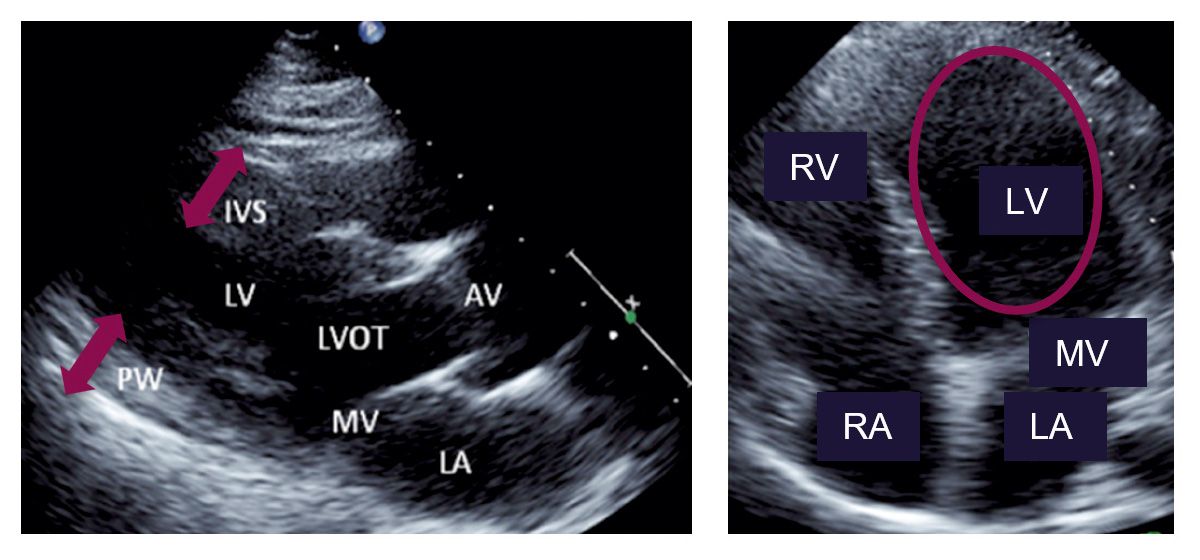

Die Echokardiographie ist das zentrale Instrument in der Diagnostik der kardialen Beteiligung bei FA. Sie ermöglicht die Beurteilung von Wanddicke, Kammergröße, systolischer und diastolischer Funktion [11].

Typischerweise findet sich bei FA eine konzentrische linksventrikuläre Hypertrophie mit einer Wanddicke von <15 mm (Abb. 3 A) [16]. Eine Obstruktion des linksventrikulären Ausflusstrakts tritt dagegen nur selten auf [16].

Im Vier-Kammer-Blick zeigt sich im weiteren Verlauf eine Dilatation des linken Ventrikels sowie eine diastolische Funktionsstörung, die lange Zeit als pseudonormal erscheinen kann [17, 21] (Abb. 3 B). Mit fortschreitender Erkrankung kommt es durch zunehmende Myokardfibrose zu einer Abnahme der Ejektionsfraktion und somit zur Entwicklung einer systolischen Dysfunktion [16].

Abb. 3: Echokardiogramme bei FA. A) Vergrößerung des interventrikulären Septums (IVS) und der posterioren Hinterwand (PW). B) Dilatation des linken Ventrikels (LV) [6]